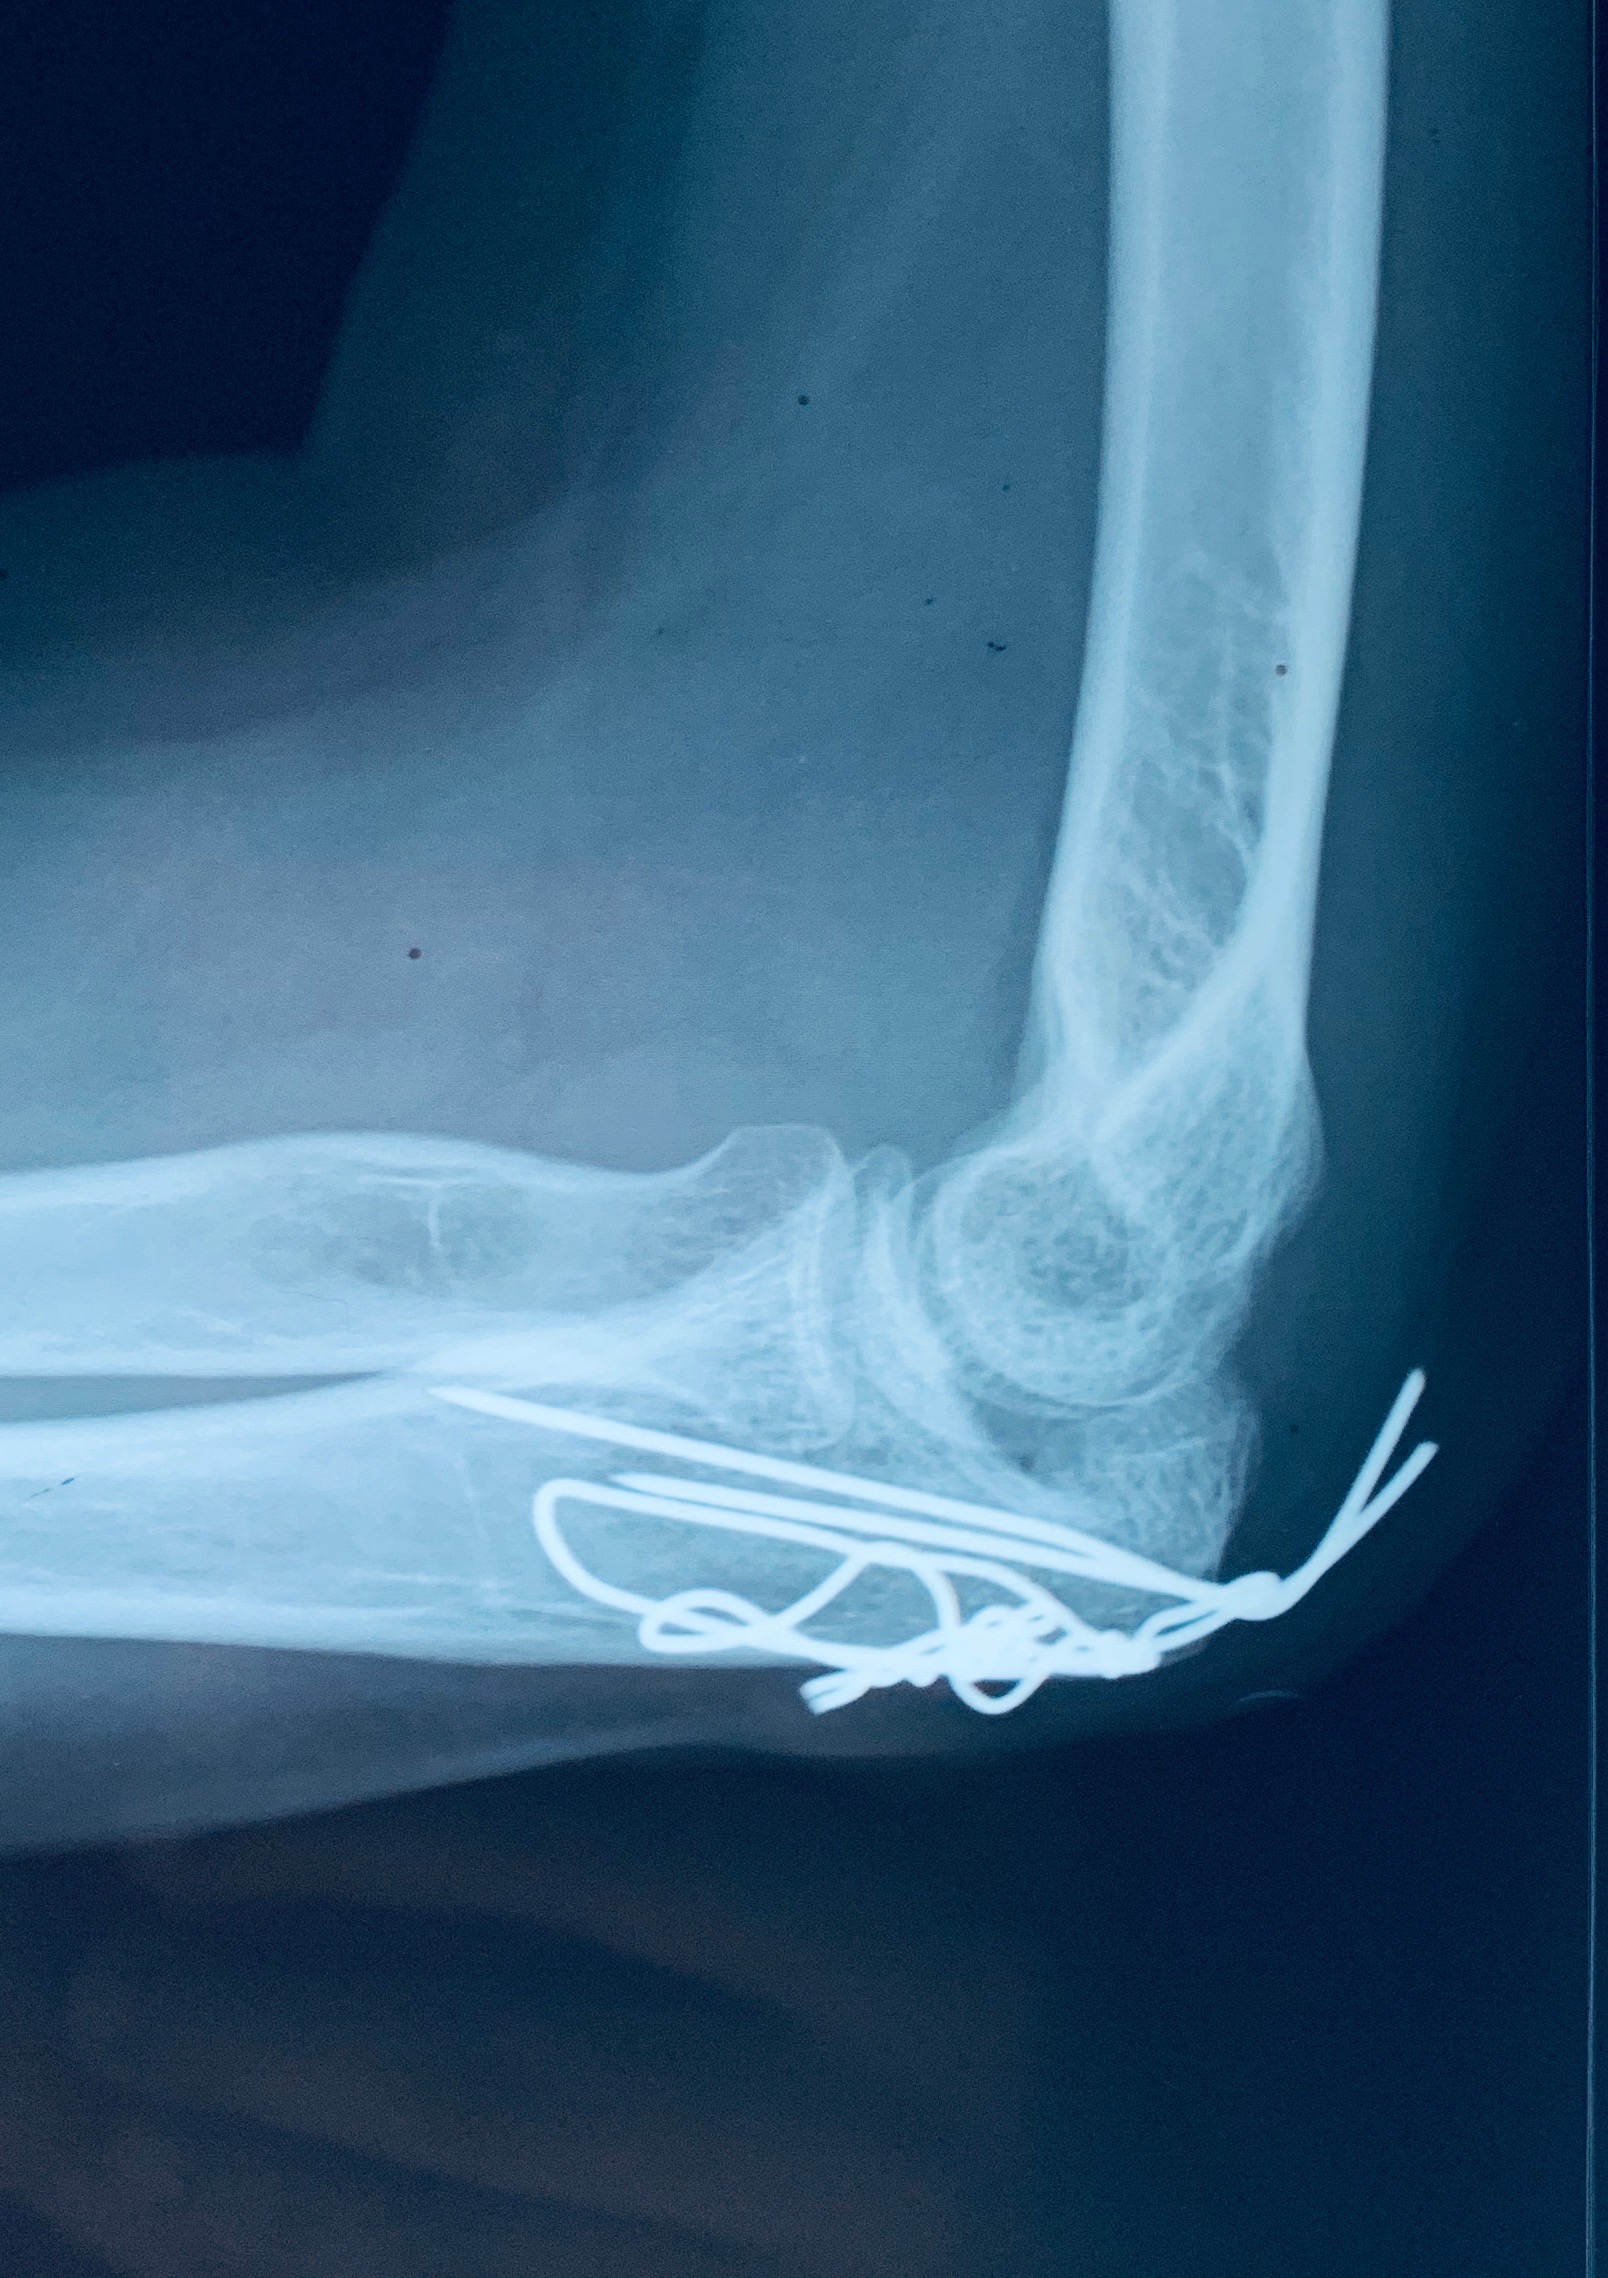

ORIF WITH TBW

A 28 year old female case of post-traumatic left-sided olecranon fracture, displaced was treated.

Surgery performed was open reduction & internal fixation with tension band wiring was done.